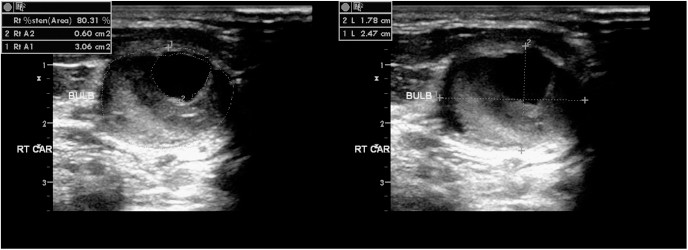

경동맥 협착증은 혈관이 좁아진 정도를 퍼센티지로 산출하여 뇌로 가는 혈류의 장애 정도를 판단할 수 있습니다.

동맥경화가 심해져 플라크가 형성되면, 작은 조각이 떨어져 나가 뇌혈관을 막으면서 허혈성 뇌졸중을 유발할 수 있습니다. 따라서 플라크 유무와 상태 파악은 예방 측면에서 매우 중요합니다. 내막 두께(IMT)는 혈관 노화 지표로, 정상치보다 두꺼워지면 심혈관 질환 발병 위험 증가를 시사합니다. 특히 당뇨병, 고혈압 환자에게서 흔히 관찰되므로 관리의 기준이 됩니다. 드물지만 동맥류나 박리 등 혈관 벽 질환도 파악할 수 있어 응급상황 예방에 도움을 줍니다. 눈으로 직접 보이지 않는 혈관이기 때문에 초음파 영상으로 구조와 흐름을 동시에 평가할 수 있다는 것이 큰 장점입니다.

- 혈관 내막 두께, 혈류 속도, 플라크 여부 등 확인